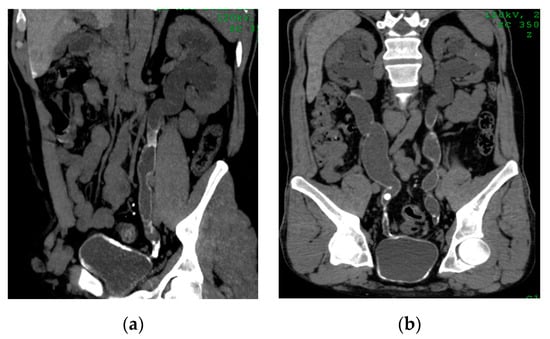

2.9. Corynebacterium Infection: Encrusted Pyelitis and Cystitis

| Encrusted pyelitis and cystitis | Linear hyperdense calcifications along the thickened urothelium. |